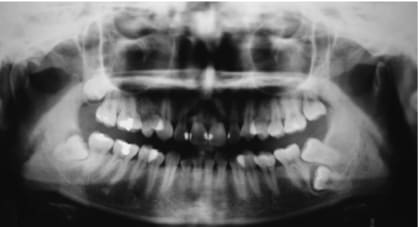

que feriez vous dans ce cas? extraire la 37 et tracter la 38 en position de la 37 ou preserver la 37 qui semble-t-il a un pronostic endodontique defavorable!

quel est le meilleur rapport benefice risque?

Vu l'état de la denture sur la pano, il faut mieux commencer par des choses simples, puis réévaluer la motivation, avant de se lancer dans un ttt multiattaches potentiellement cariogène.

A mon sens, on ne peut pas juger du pronostic de la 37 sans y être allé voir.